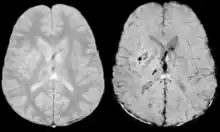

Gradient recalled echo (GRE) imaging is the conventional way to detect hemorrhage in CAA, however SWI is a much more sensitive technique that can reveal many micro-hemorrhages that are missed on GRE images.[7] A conventional gradient echo T2*-weighted image (left, TE=20 ms) shows some low-signal foci associated with CAA. On the other hand, an SWI image (center, with a resolution of 0.5 mm x 0.5 mm x 2.0 mm, projected over 8mm) shows many more associated low-signal foci. Phase images were used to enhance the effect of the local hemosiderin build-up. An example phase image (right) with yet higher resolution of 0.25 mm x 0.25 mm x 2.0 mm shows a clear ability to localize multiple CAA-associated foci.